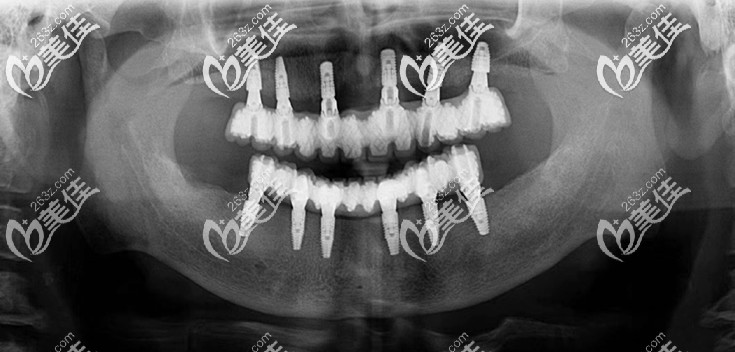

【沈阳欢乐口腔医院——孙乃鹤医生全口种植牙案例对比图赏析】:

62岁的张阿姨,全口牙缺失已经多年,这期间活动假牙戴了6年,近两年,看到身边的人做完种植牙后,啃排骨吃苹果都像真牙一样,自己就在牌友的介绍下来沈阳欢乐口腔做了全口种植牙,种完牙后,张阿姨自称道,如果不是种植牙价格贵,前几年自己早就做种牙了,没想到两年后,自己还是选择了种牙,不过做完种植牙后,吃东西实在是方便多了,和真牙有得一拼了。